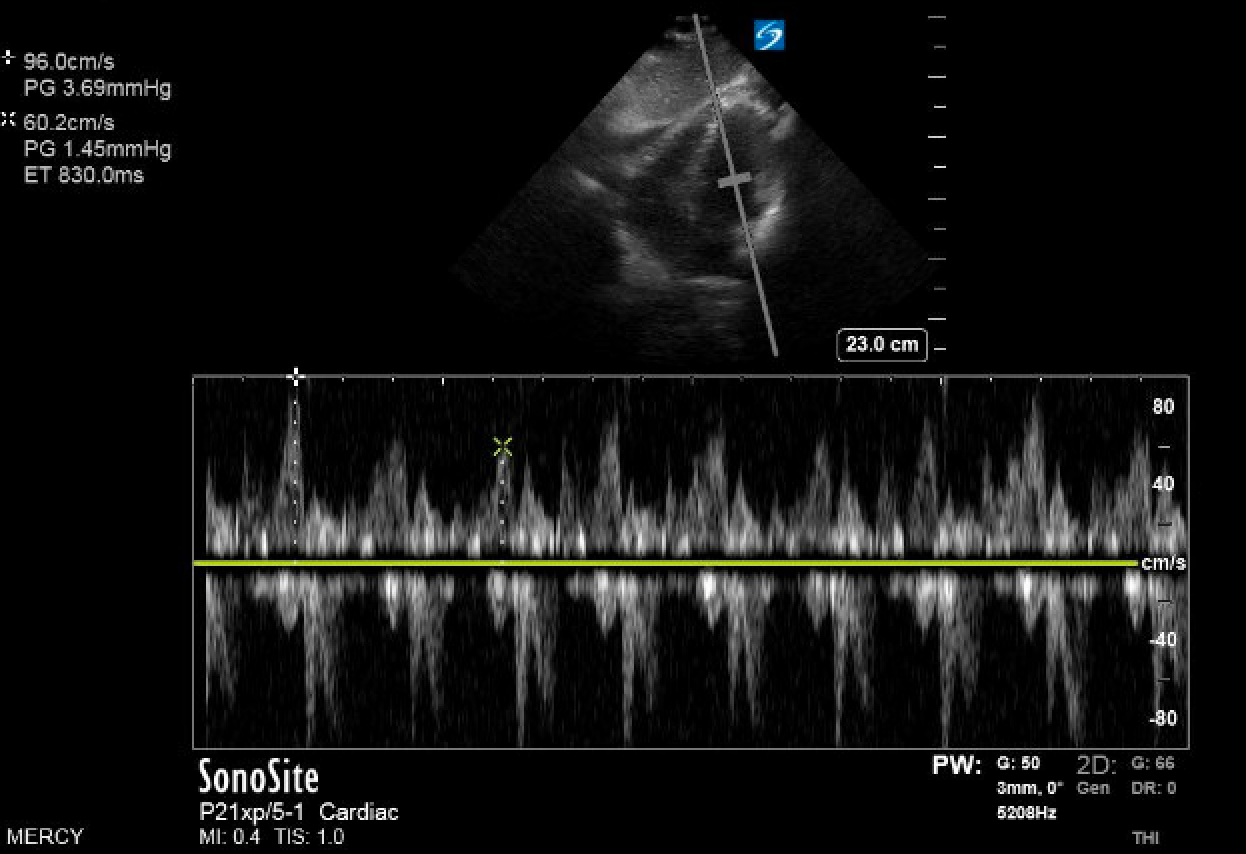

Figure 1. (A) Mitral valve inflow (MVI) velocity variation measured prior to chest thoracostomy. In this patient, MVI velocity variation is elevated at 37.5 percent, which is indicative of tamponade physiology. (B) Normalized MVI velocity variation after chest tube thoracostomy.

Under ultrasound guidance, a left tube thoracostomy was placed with evacuation of approximately two liters of serosanguinous fluid, resulting in marked improvement and near complete correction of abnormal vitals. A repeat bedside ECG showed complete resolution of tamponade findings (Figure 2), no appreciable pericardial effusion, and relocation of the heart to typical anatomic location.